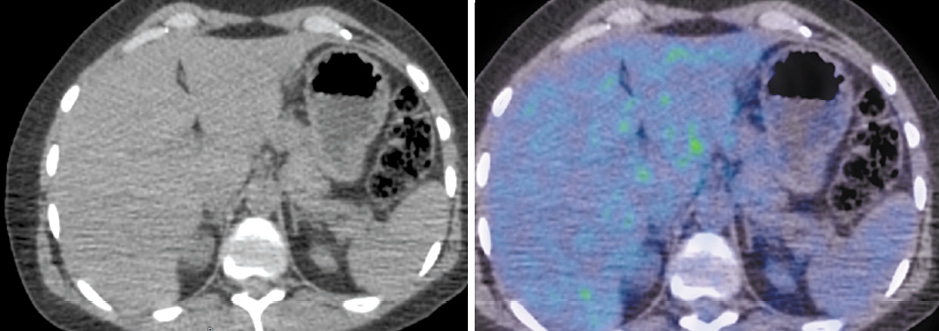

В медиальной ножке левого надпочечника имеется образование размером 16×13 мм с фиксацией 18F-ФДГ, SUVmax – 8,78 (рис. 2). Кроме того, выявлены множественные очаги патологической фиксации РФП на фоне литической перестройки костной ткани в грудинных концах ключиц, грудине, крыле левой и правой подвздошных костей, грудных позвонках, головке правой плечевой кости и большом вертеле левой бедренной кости.

Рис. 2. Пациентка Б., 41 год. ПЭТ/КТ с 18F-ФДГ до начала лечения. На аксиальных КТ- и ПЭТ/КТ-проекциях определяется образование медиальной ножки левого надпочечника размером 16×13 мм с фиксацией РФП, SUVmax – 8,78. / Fig. 2. Female patient B., 41 years old. PET/CT with 18F-FDG before the treatment. Axial CT and PET/CT views reveal a mass of the left adrenal gland medial limb of 16×13 mm with a radiopharmaceutical uptake with SUVmax of 8.78.

Рис. 4. Пациентка Б., 41 год. ПЭТ/КТ с 18F-ФДГ по окончании 6 циклов полихимиотерапии. На аксиальных КТ- и ПЭТ/КТ-проекциях образование в области медиальной ножки левого надпочечника не определяется, регрессировало. / Fig. 4. Female patient B., 41 years old. PET/CT with 18F-FDG at the end of 6 cycles of polychemotherapy. Axial CT and PET/CT views showed no mass in the area of the left adrenal gland medial limb; the mass regressed.